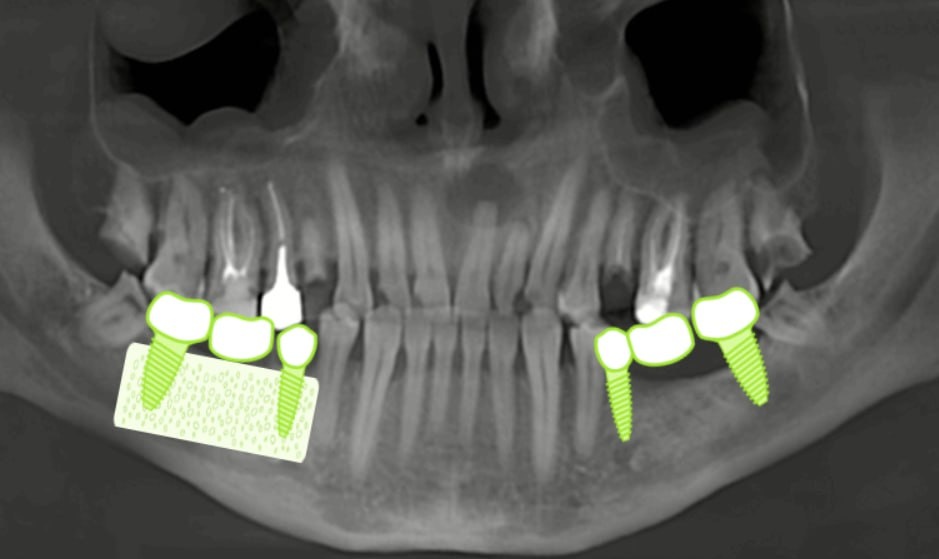

Обычные схемы зубов — это хорошо, но показать будущие манипуляции прямо на панорамном снимке пациента — куда нагляднее и понятнее.

Чтобы это стало возможным, нужно совместить снимок пациента с иллюстрациями — и в этом помогает инструмент разметки.

— Вы загружаете снимок пациента.

— На нем размечаете зубы для иллюстраций.

— Каждую иллюстрацию можно масштабировать, двигать, поворачивать — всё, чтобы точно совпало с анатомией.